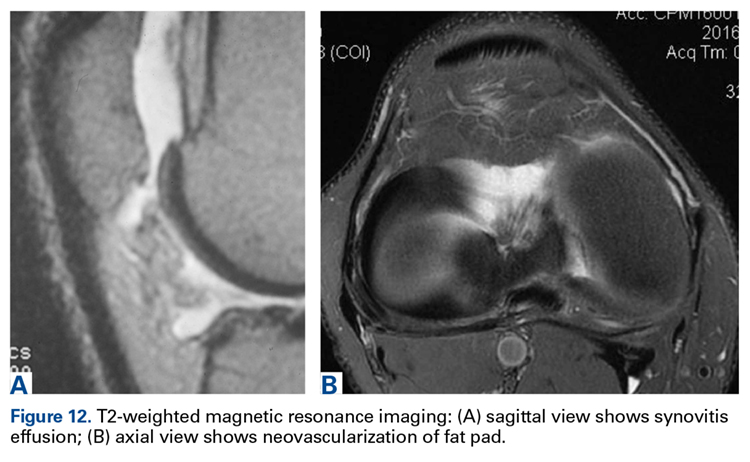

MRI can be useful, though scans are commonly read as normal. In some cases, MRI evidence of tendinopathy and other intra-articular pathology can direct both operative and nonoperative treatment of AKP. Carefully look for evidence of soft-tissue impingement—such as mild synovial swelling, low-grade effusion, and neovascularization of the fat pad—as in many cases it exists, and has been missed by the radiologist (Figures 12A, 12B).

View the images yourself and, if necessary, in consultation with a radiologist.When Surgery Is Needed: General Principles